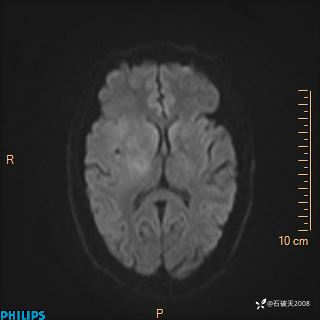

2020.11.14MR

ADC